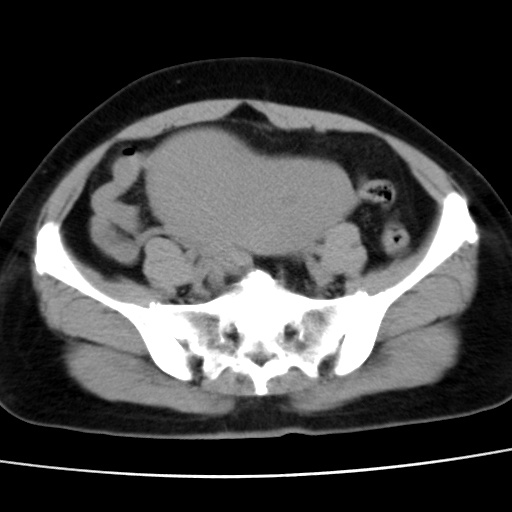

子宫多发肌瘤吗

多发性子宫肌瘤.

考虑多发子宫肌瘤,子宫直肠窝双囊性占位,另直肠周围脂肪密度增高,不知有何病史

支持考虑多发子宫肌瘤~!子宫直肠陷凹积液?

支持考虑多发子宫肌瘤~!子宫直肠陷凹积液!

子宫肌瘤,宫体部后方见液性密度影,是肠道还是子宫与直肠陷窝积液不好说,我觉得它的位置有点高

支持考虑多发子宫肌瘤!子宫直肠陷凹积液!

患者发热,而子宫直肠窝液性灶有明显边缘且局限且囊性,不除外为包裹性积液或脓肿

支持考虑多发子宫肌瘤,子宫直肠陷凹积液可能。

考虑多发子宫肌瘤

1)考虑子宫肌瘤可能性大。2)子宫后方囊性占位性病变,不排除卵巢囊肿可能。

考虑多发子宫肌瘤。子宫后方囊性占位性病变,不排除卵巢囊肿可能。